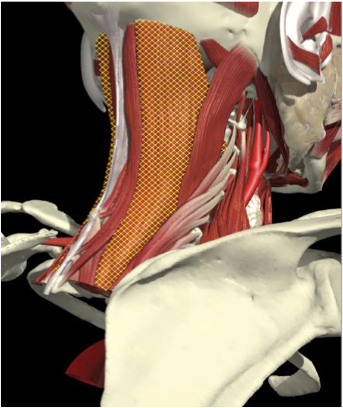

LATEROCOLLIS

Long muscles transversing spine

- Levator scapulae

- Scalenus Anterior/medius

- Semispinalis cervicis

- Longissimus cervicis

Biomechanical advantage

- Range - 37 degrees

LATEROCAPUT

Muscles that insert into skull (mastoid/ occiput)

- Trapezius

- Sternomastoid

- Splenius capitus/cervicus

- Longissimus capitus

Range of movement

- 8 degrees